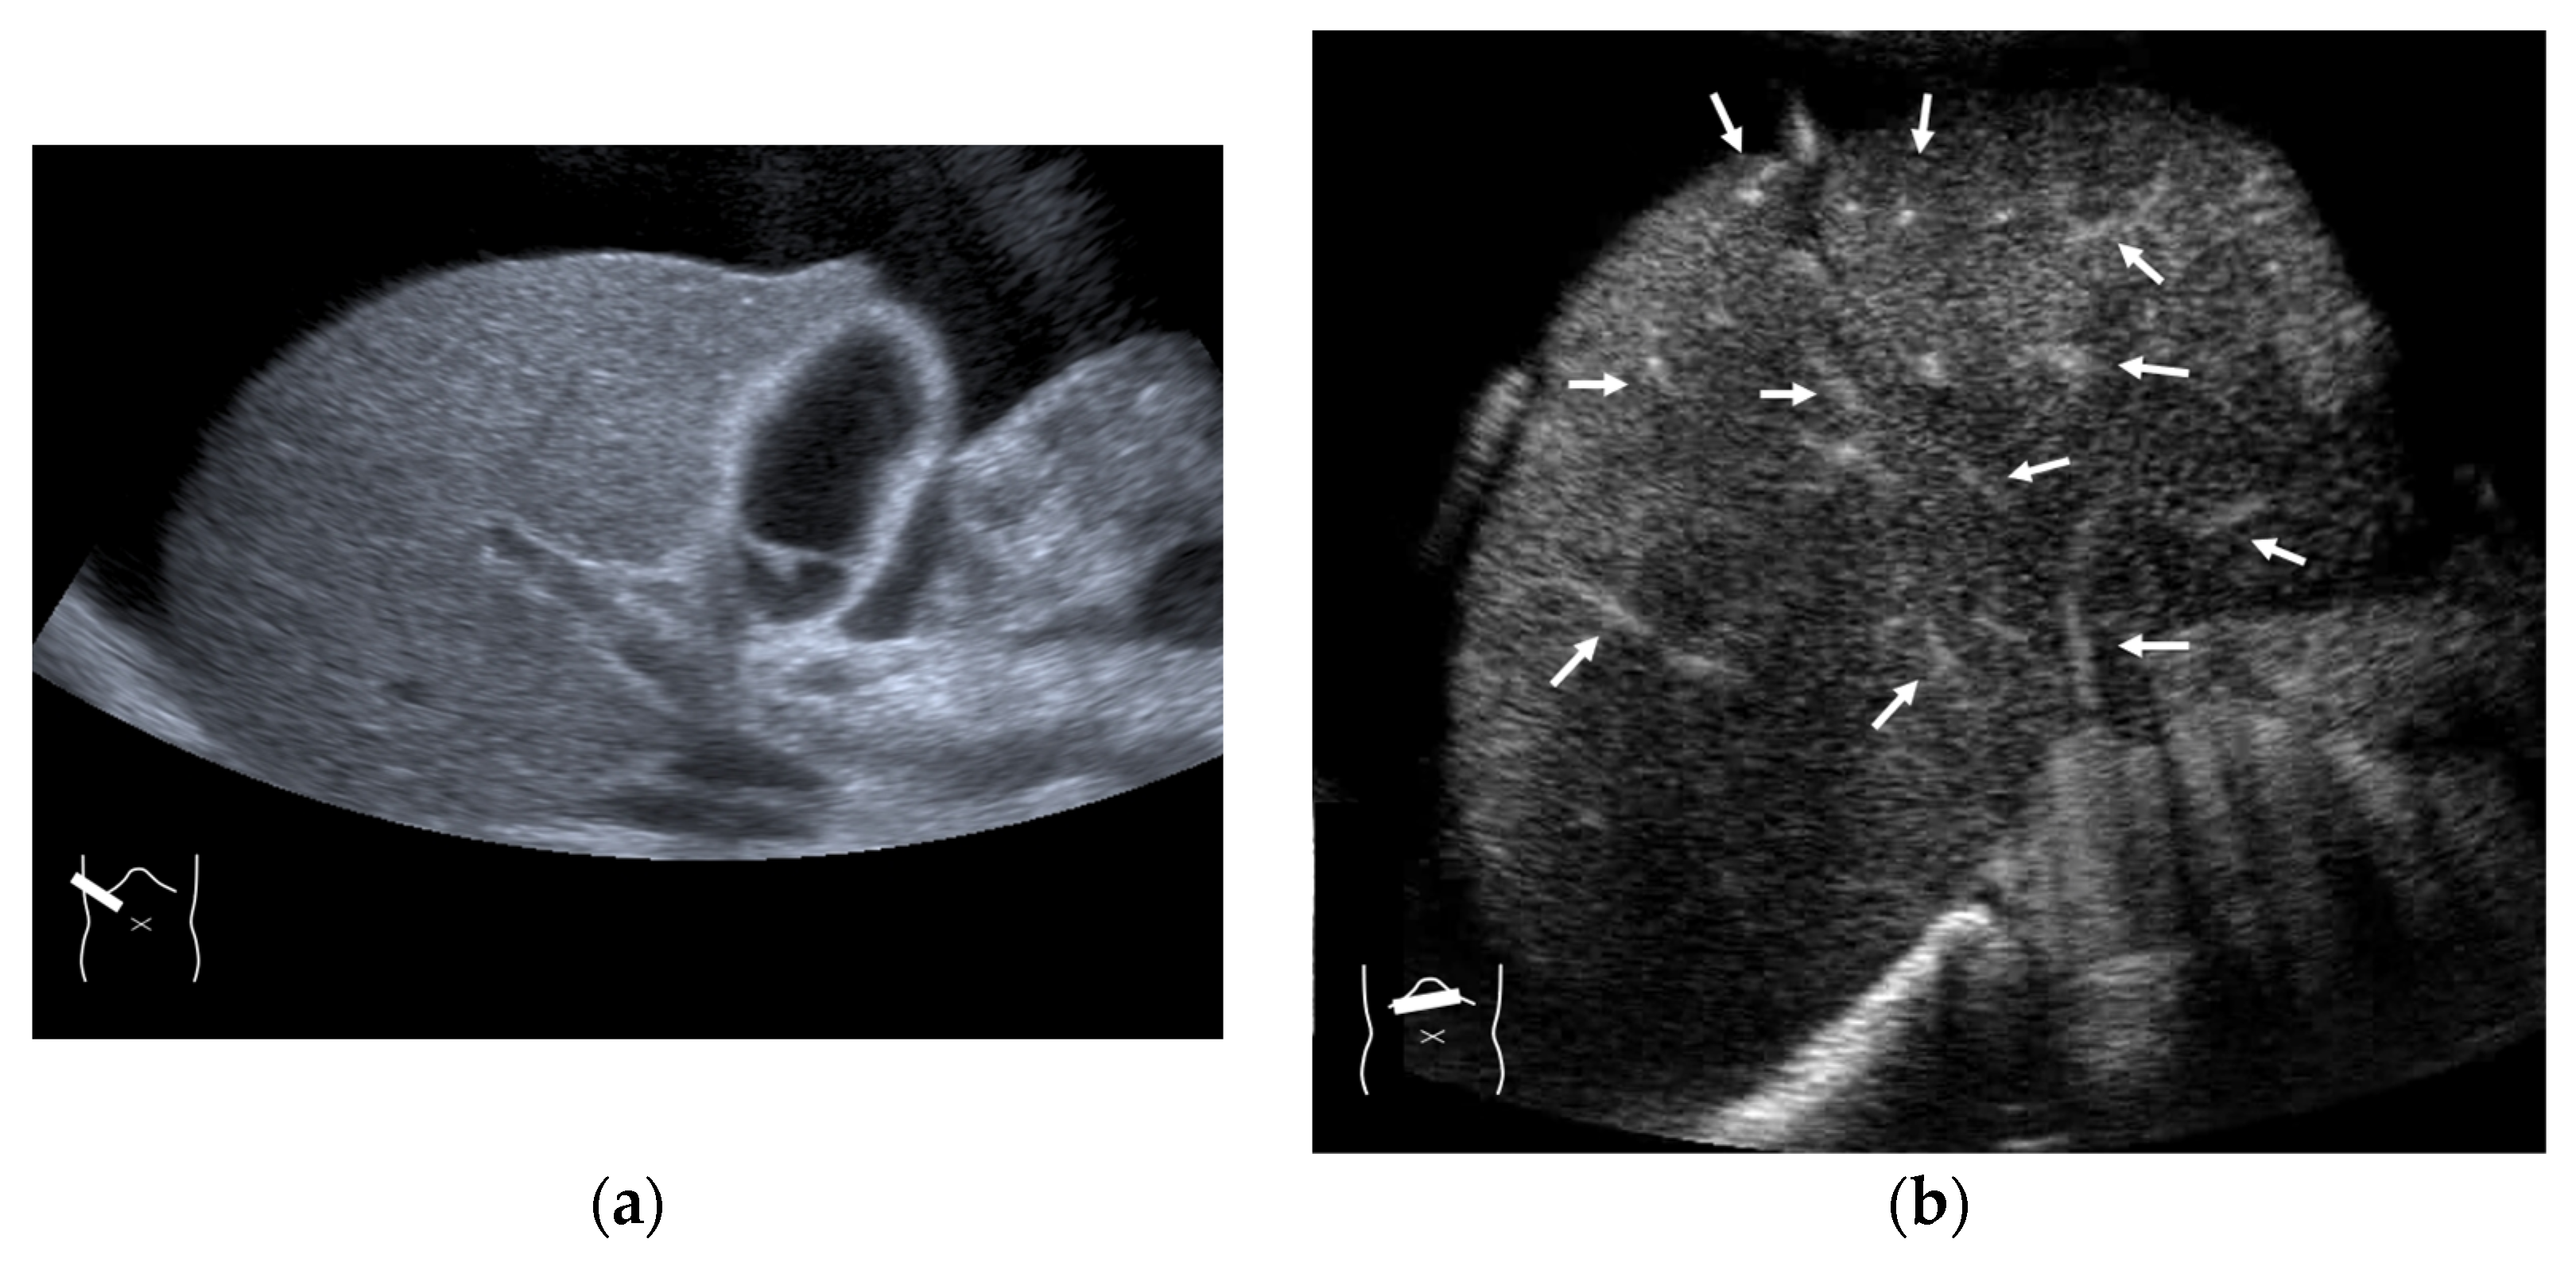

Figure 14.

Representative case of chemotherapy-induced sinusoidal obstruction syndrome: (a) B-mode US shows that the liver has a homogeneous texture. (b) CEUS shows that all hepatic veins and portal veins are simultaneously enhanced (arrows).